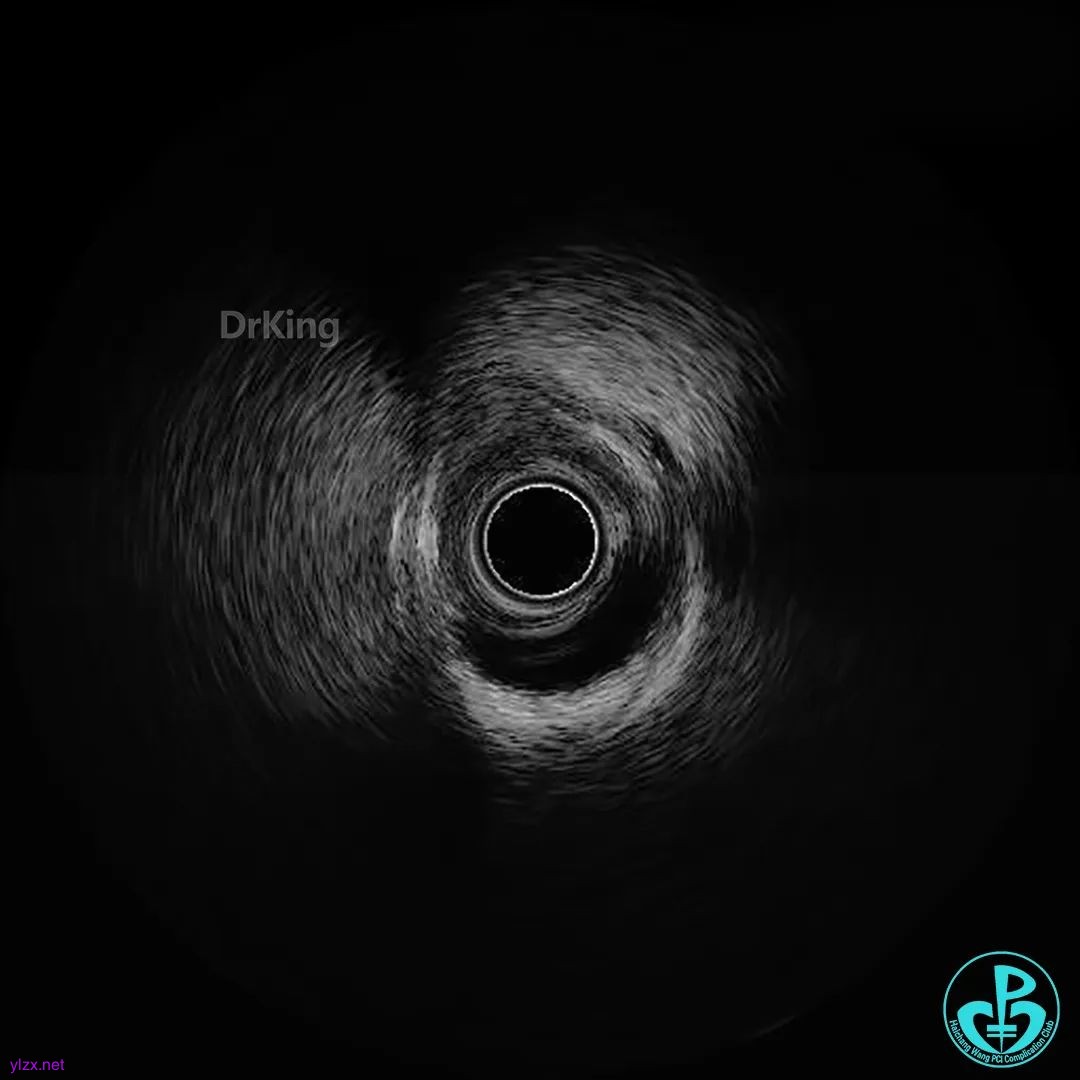

患者出现胸痛,给予镇痛治疗,同时考虑血管内超声检查。

超声证实PL延伸至近端血肿,近端可见夹层破口。